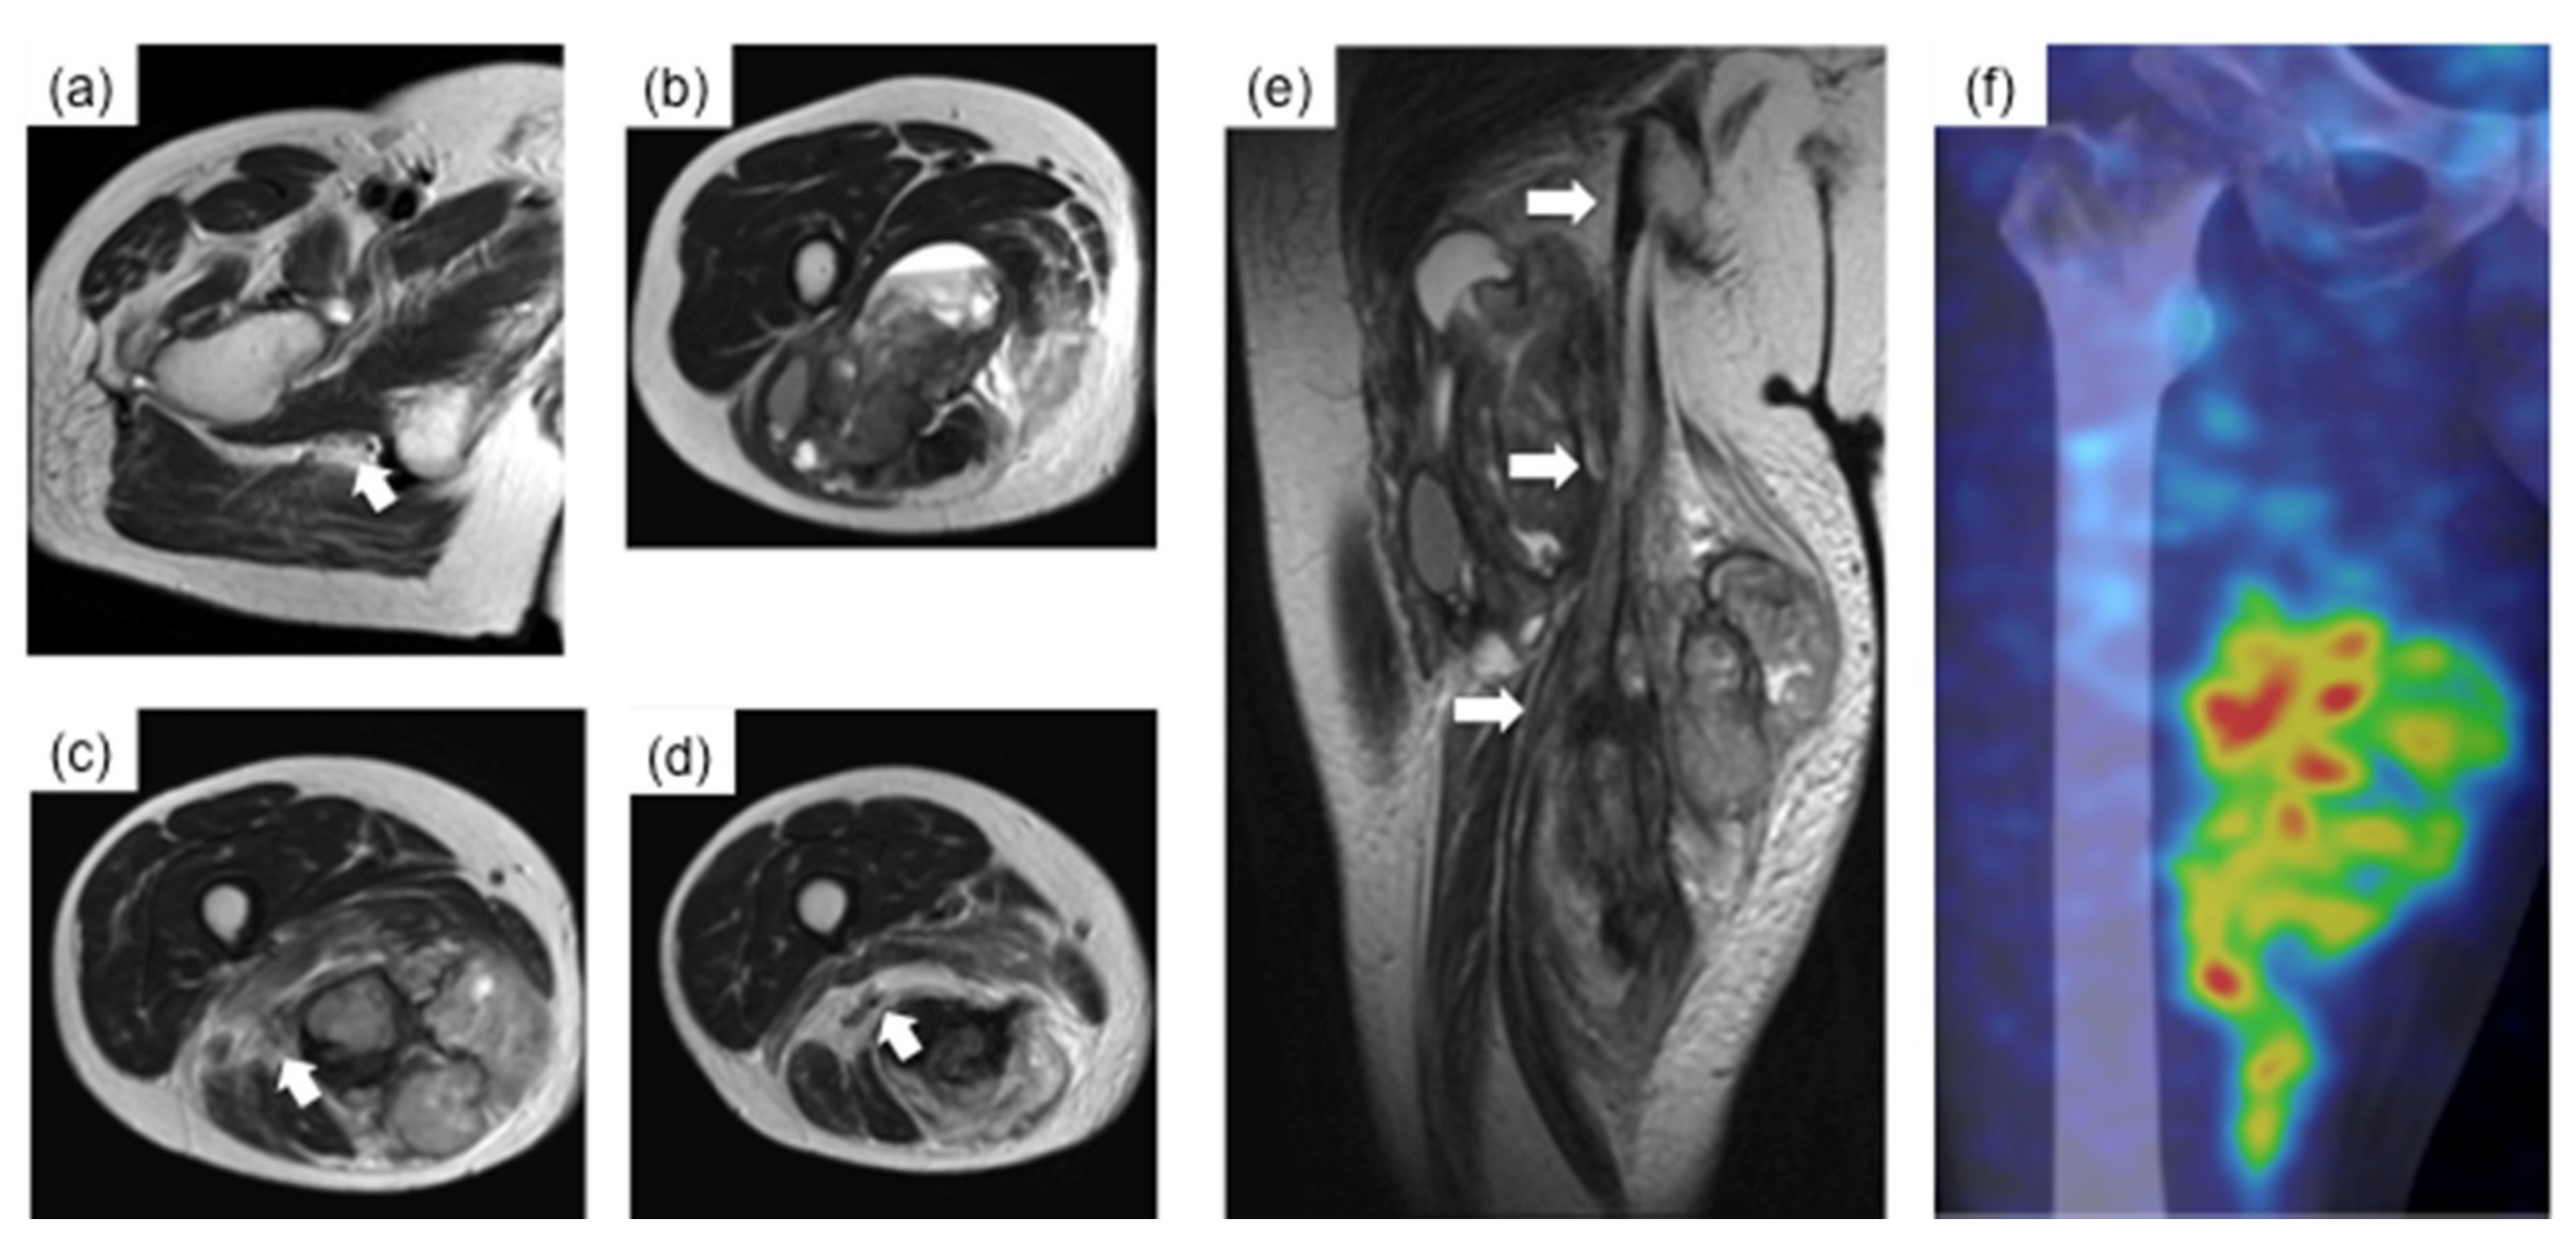

2. Case Presentation